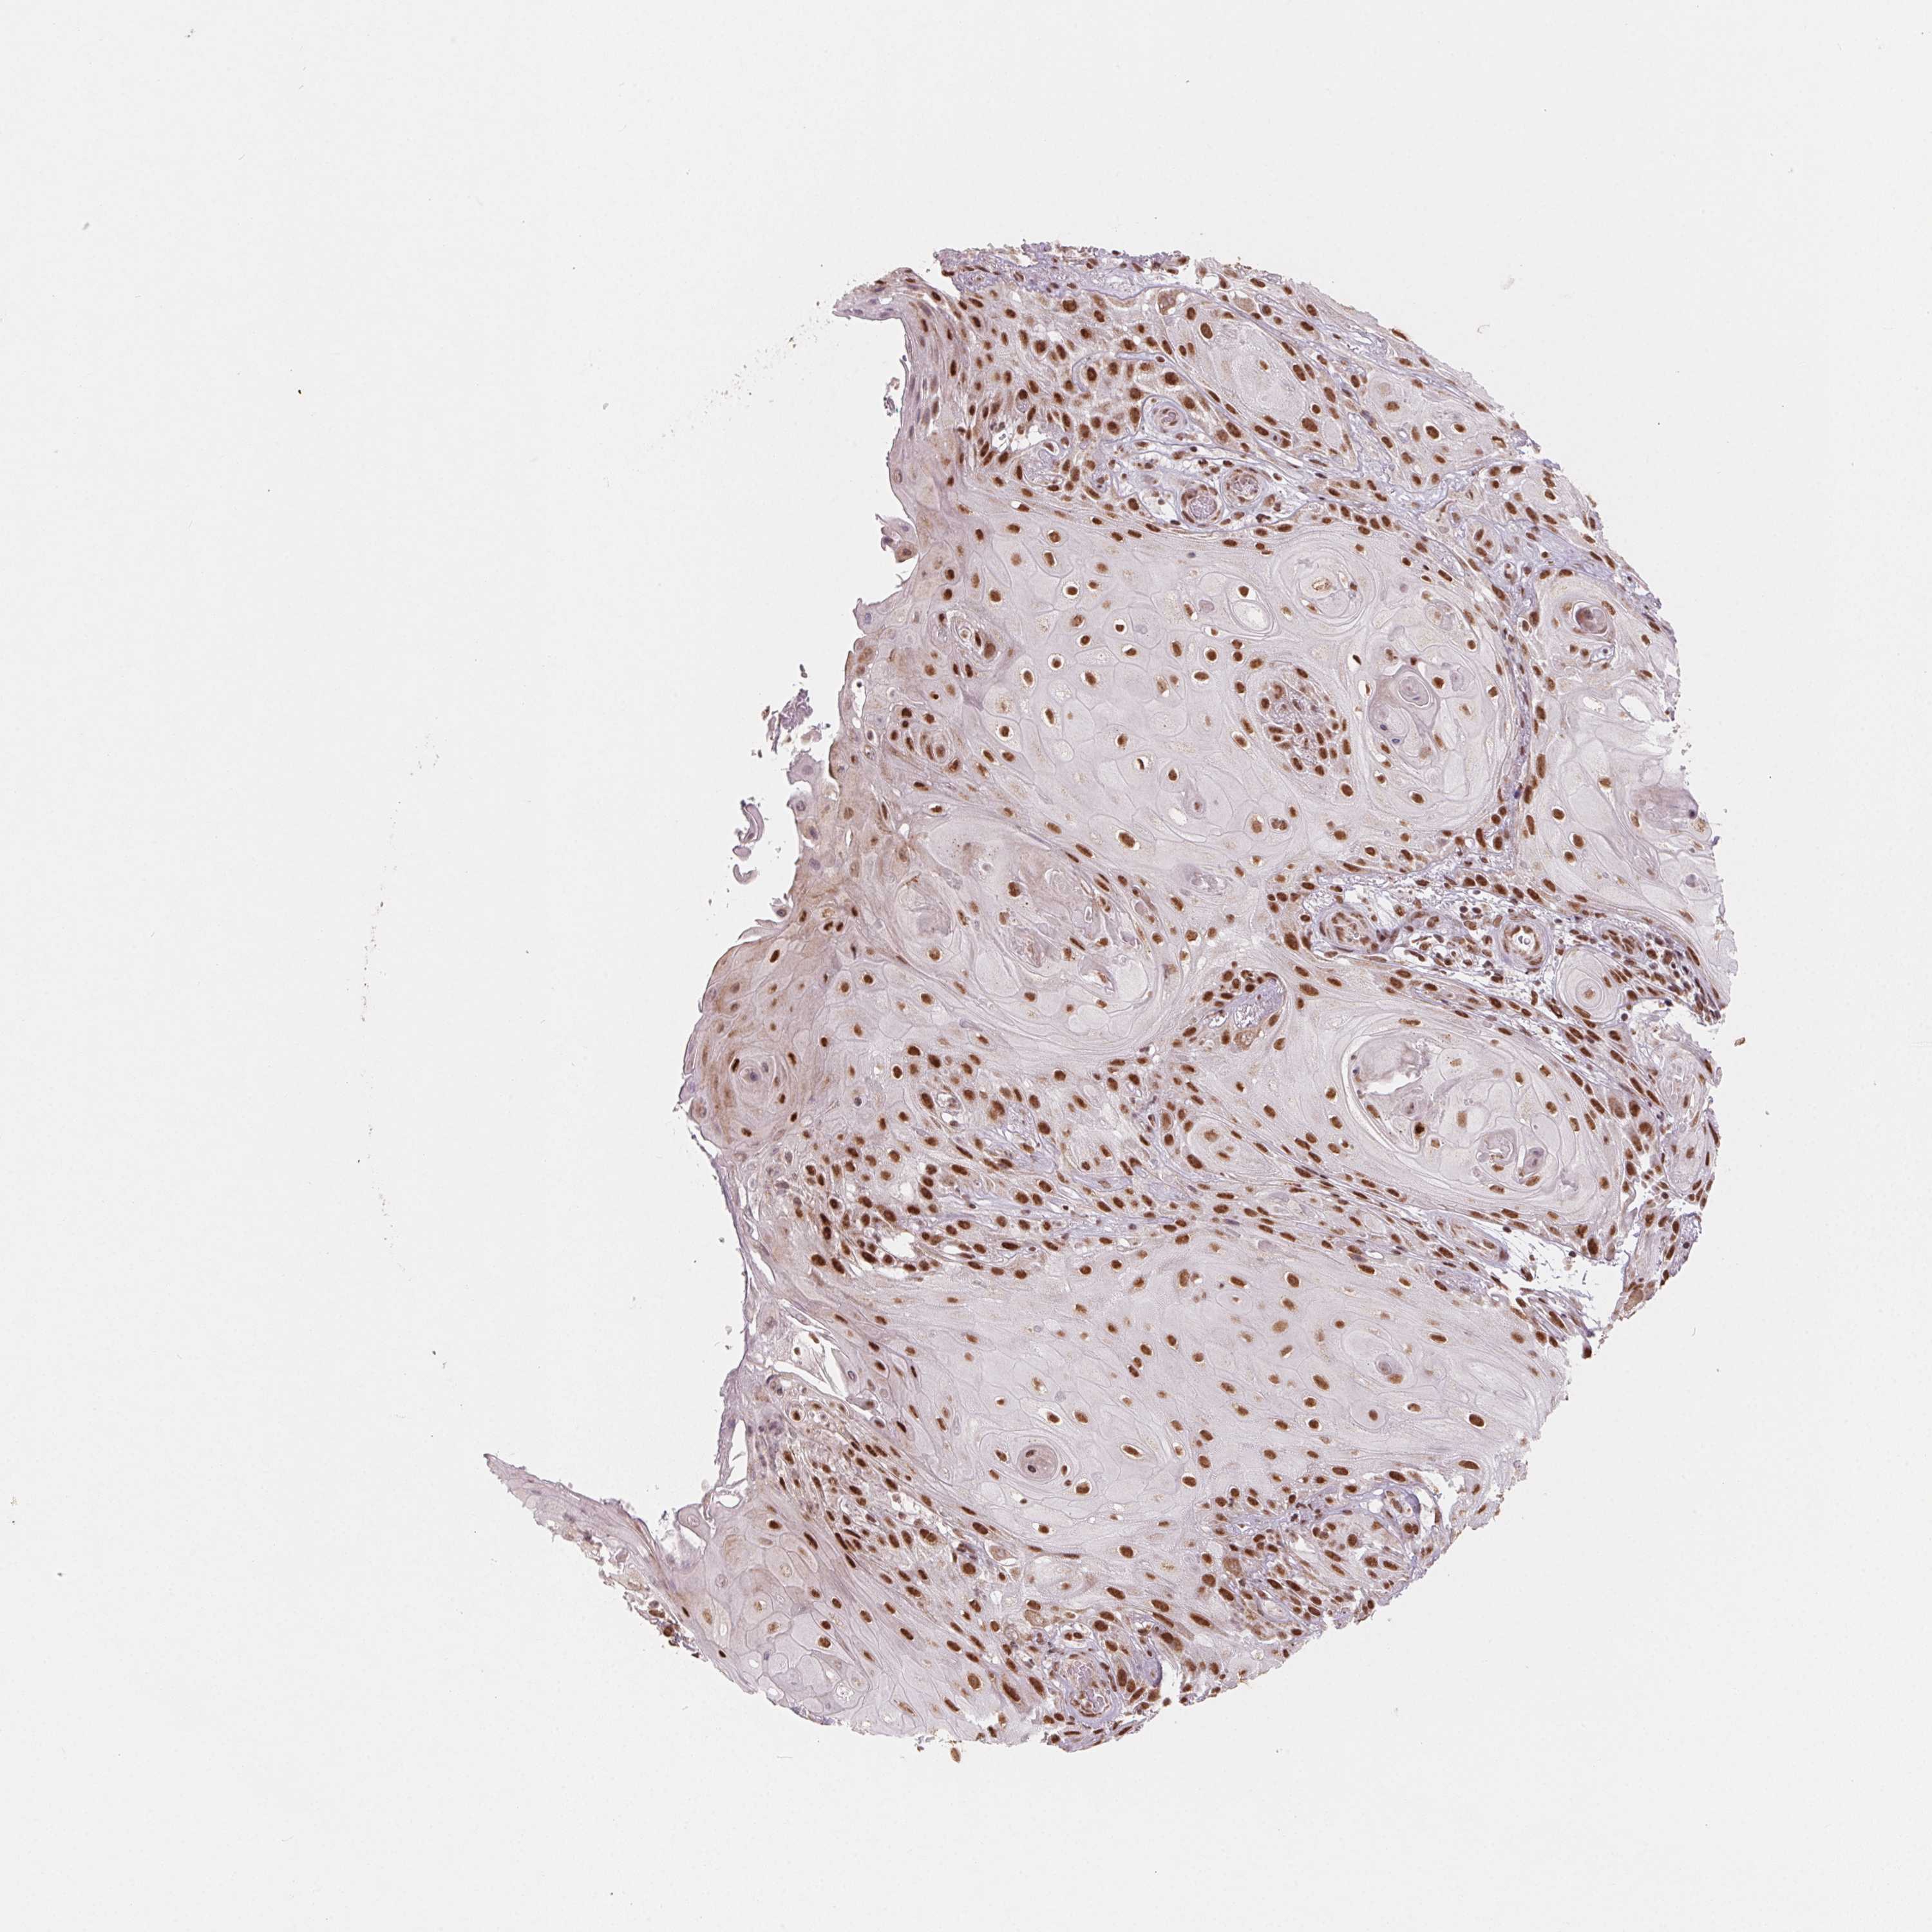

SKIN CANCER - Protein expressioni

A mouse-over function shows sample information and annotation data. Click on an image to view it in a full screen mode. Samples can be filtered based on level of antibody staining by selecting one or several of the following categories: high, medium, low and not detected. The assay and annotation is described here.

Antibody stainingi

Antibody staining in the annotated cell types in the current human tissue is reported as not detected, low, medium, or high, based on conventional immunohistochemistry profiling in selected tissues. This score is based on the combination of the staining intensity and fraction of stained cells.

Each image is clickable and will lead to virtual microscopy that enables deeper exploration of all samples and also displays staining intensity scores, fraction scores and subcellular localization as well as patient and tissue information for each sample.

Antibody HPA065661

Staining

High

Medium

Low

Not detected

Intensity

Strong

Moderate

Weak

Negative

Quantity

>75%

75%-25%

<25%

None

Location

Nuclear

Cytoplasmic/membranous

Cytoplasmic/membranous,nuclear

Basal cell carcinoma

Squamous cell carcinoma, NOS